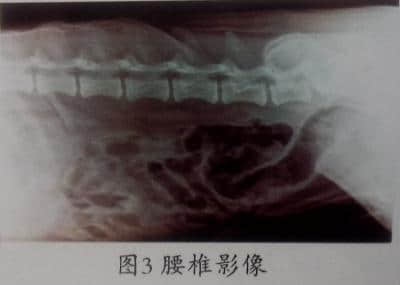

第5天,进行X-ray检查,主要检查椎体系统,包括颈椎、胸椎、腰椎,影像见图1、图2、图3。

X-ray显示,胸腰椎联合处的第1、第2、第3腰椎椎间间隙不均匀,由此证实第1、第2、第3腰椎椎间盘脱出,进而压迫神经引起后躯的麻痹及瘫痪,故确诊为腰椎间盘突出引起的瘫痪。